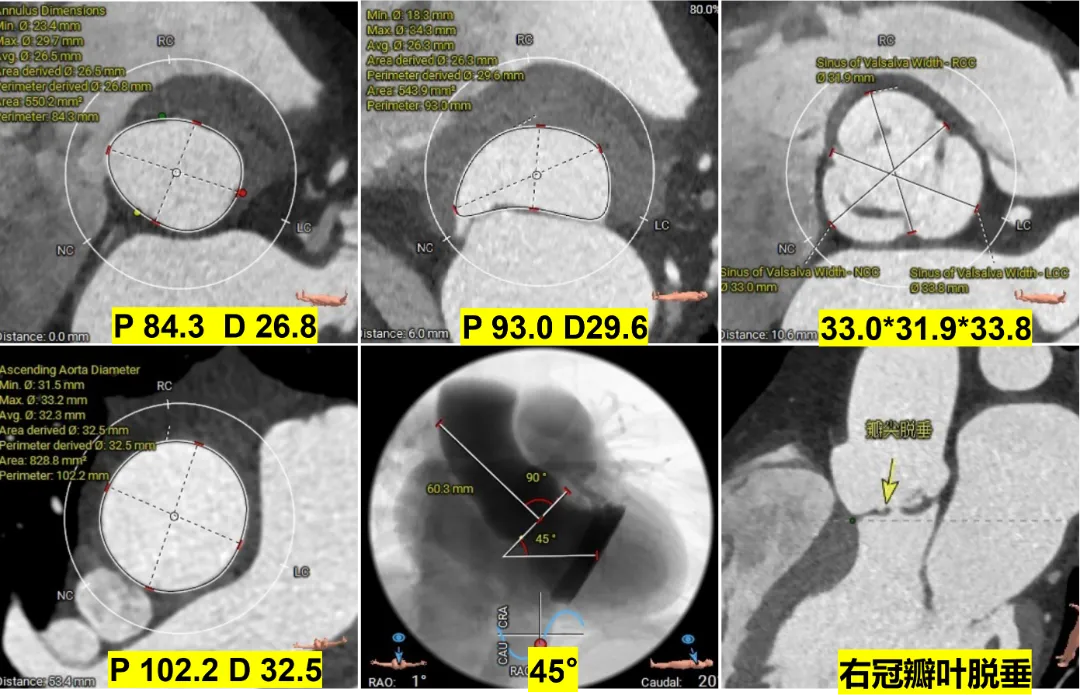

术前CT评估

根据瓣环与 LVOT-6 mm 平面,选择:M 号 TaurusTrio,瓣环可提供4.3%oversize

根据瓣环与 LVOT-6 mm 平面,选择:M 号 TaurusTrio,瓣环可提供7.3%oversize